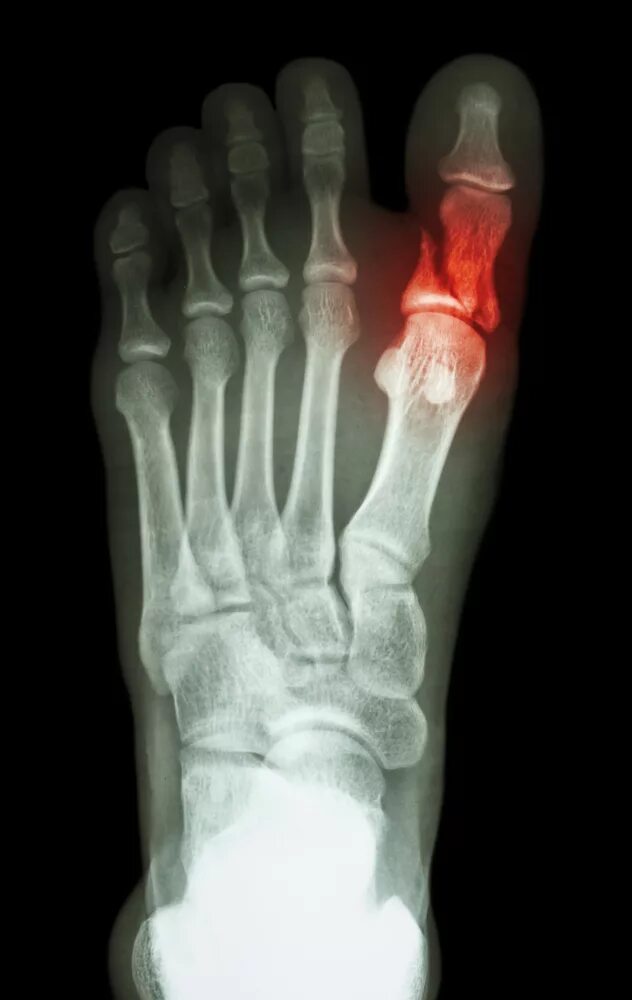

Закрытый перелом пальцев стопы мкб 10